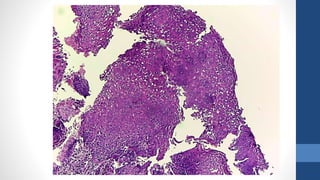

Mujer de 23 años, biopsia de cervix

Diagnóstico

•LIE de alto grado, NIC 2

• El precursor directo del cáncer cervical es la lesión de alto grado (también conocido

como NIC 2 y NIC 3) el cual puede progresar a cáncer en un periodo de hasta 10 ó

más años. La mayoría de lesiones de bajo grado desaparecen sin tratamiento o no

avanzan, sobre todo en mujeres jóvenes. Sin embargo, los casos que ocurren en

países en donde no hay programas de tamizaje en funcionamiento y la enfermedad

ha estado presente durante periodos de tiempo más largos, son menos probable de

regresionar o desaparecer.